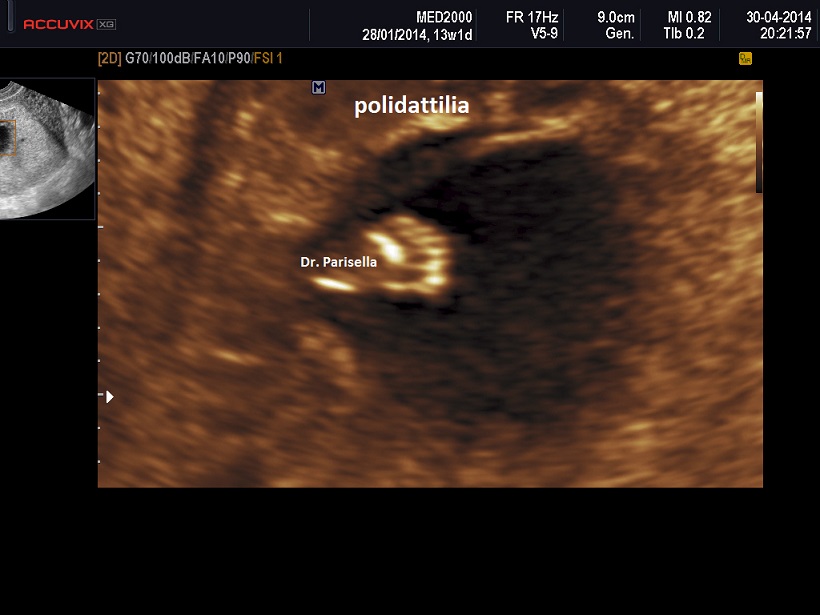

All'esame ecografico prenatale le caratteristiche che indirizzano verso la diagnosi sono:

3) la polidattilia è di tipo postassiale ed è pressocchè costante alle mani